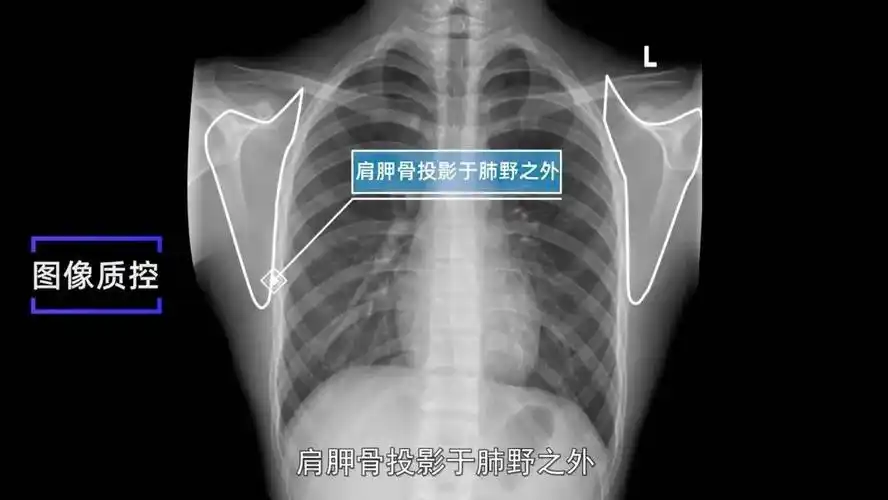

ap in internal rotation肩胛骨内旋正位六ap view 肩关节正位(胸片位

肩胛骨投影于肺野之外.3. 肺尖充分显示.2.